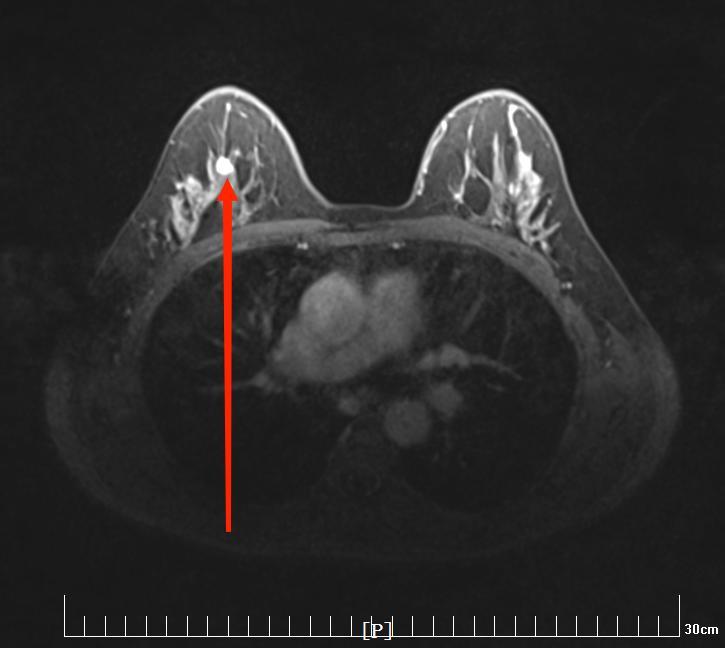

患者吴姐(化名)因为体检发现右侧乳房有结节4天来我院就诊,行乳腺超声检查,结果提示:右乳11点位结节,8.6×5.3mm,BI-RADS 4C(图1);乳腺MRI增强扫描示:右乳肿块,7×6mm大小,BI-RADS 5(图2)。

图2. 磁共振提示右乳肿块,红色箭头所指处为肿块